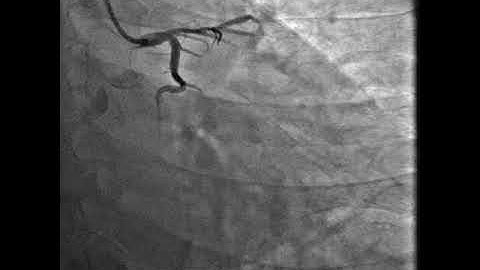

Deficult scenario during p pci. culprit LCX. non Culprit LMS and LAD.